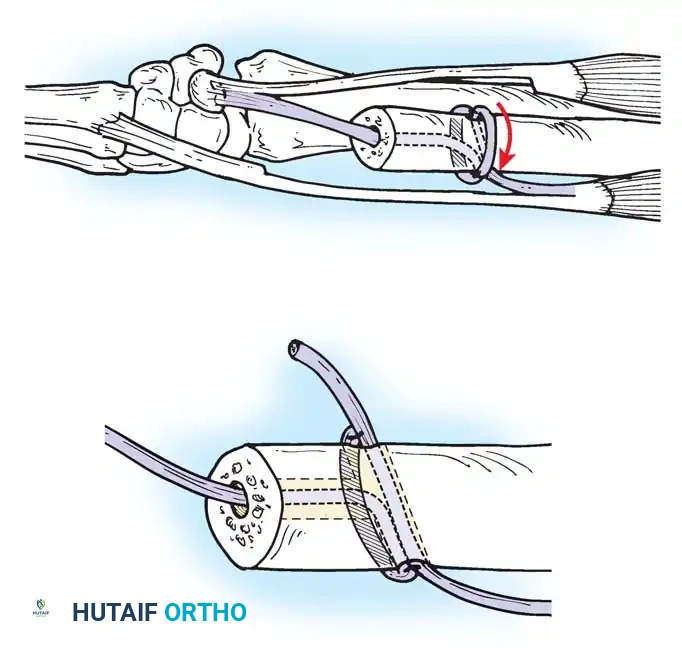

Passing non-absorbable sutures through the osseous tunnels in the ulna to capture the peripheral edge of the TFCC.

- Pass strong, non-absorbable sutures (e.g., 2-0 FiberWire) through the TFCC using an outside-in or inside-out technique, then shuttle the suture limbs down the osseous tunnels.

The sutures are tied securely over the cortical bone bridge of the ulnar neck, restoring tension to the radioulnar ligaments.

- Tie the sutures over the ulnar cortical bridge with the forearm in neutral rotation to restore anatomic tension.

In chronic settings where the TFCC is irreparable, anatomic ligament reconstruction using a tendon autograft (e.g., palmaris longus) is indicated. The graft is routed through the distal radius and ulnar fovea to recreate the dorsal and volar radioulnar ligaments.

Tendon graft routing through osseous tunnels in the radius and ulna for anatomic reconstruction of the DRUJ ligaments.